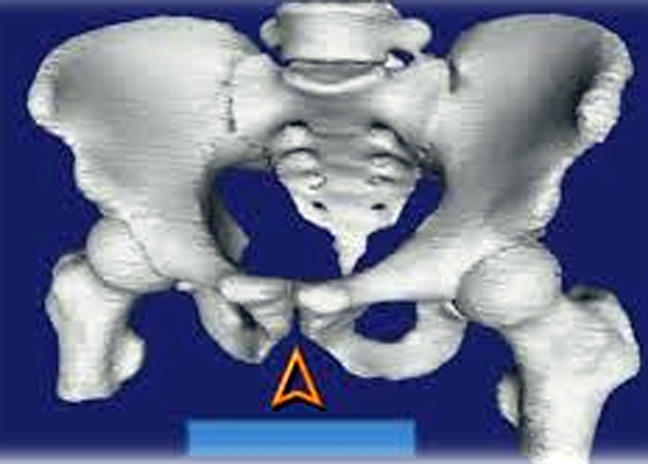

Η ηβική σύμφυση είναι το πρόσθιο ανατομικό στοιχείο της λεκάνης όπου το ένα λαγόνιο μέσω των ηβοϊσχιακών κλάδων «κλείνει» το δακτύλιο της λεκάνης «ακουμπώντας» την απέναντι πλευρά.

Η ηβική σύμφυση είναι μία συνδέσμωση, δηλαδή μία άρθρωση χωρίς κίνηση, που επιτρέπει απλώς μικροκινήσεις στη διάρκεια του τοκετού.

Φυσικά σε βαρείες κακώσεις της λεκάνης με κάταγμα των λαγονίων και περιστροφήτότε εκτός από υπεξάρθρημα των ιερολαγονίων, συνυπάρχει και υπεξάρθρημα (τραυματικό) της ηβικής σύμφυσης.